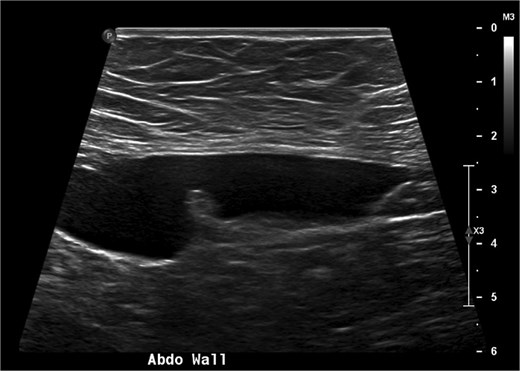

A 38-year-old woman presented to clinic with chronic supraumbilical abdominal pain. This was not associated with any gastrointestinal or constitutional symptoms, or systemic unwellness. She did not have any significant medical history. She had a Caesarean section 5 years prior. On examination, a large mass was palpated in the supraumbilical area; there was a small reducible fat-containing umbilical hernia, and there were no signs of peritonism. Blood tests including serum tumour markers were unremarkable. Computed tomography (CT) of the abdomen revealed an 8 × 3 cm hypodense lesion just deep to the anterior abdominal wall (Fig. 1). An ultrasound (USS) characterised this lesion as an 8 × 7 × 3 cm cyst with simple internal contents suggestive of a falciform ligament cyst (Fig. 2).

A USS image showing the 8 cm falciform ligament cyst with simple internal contents.